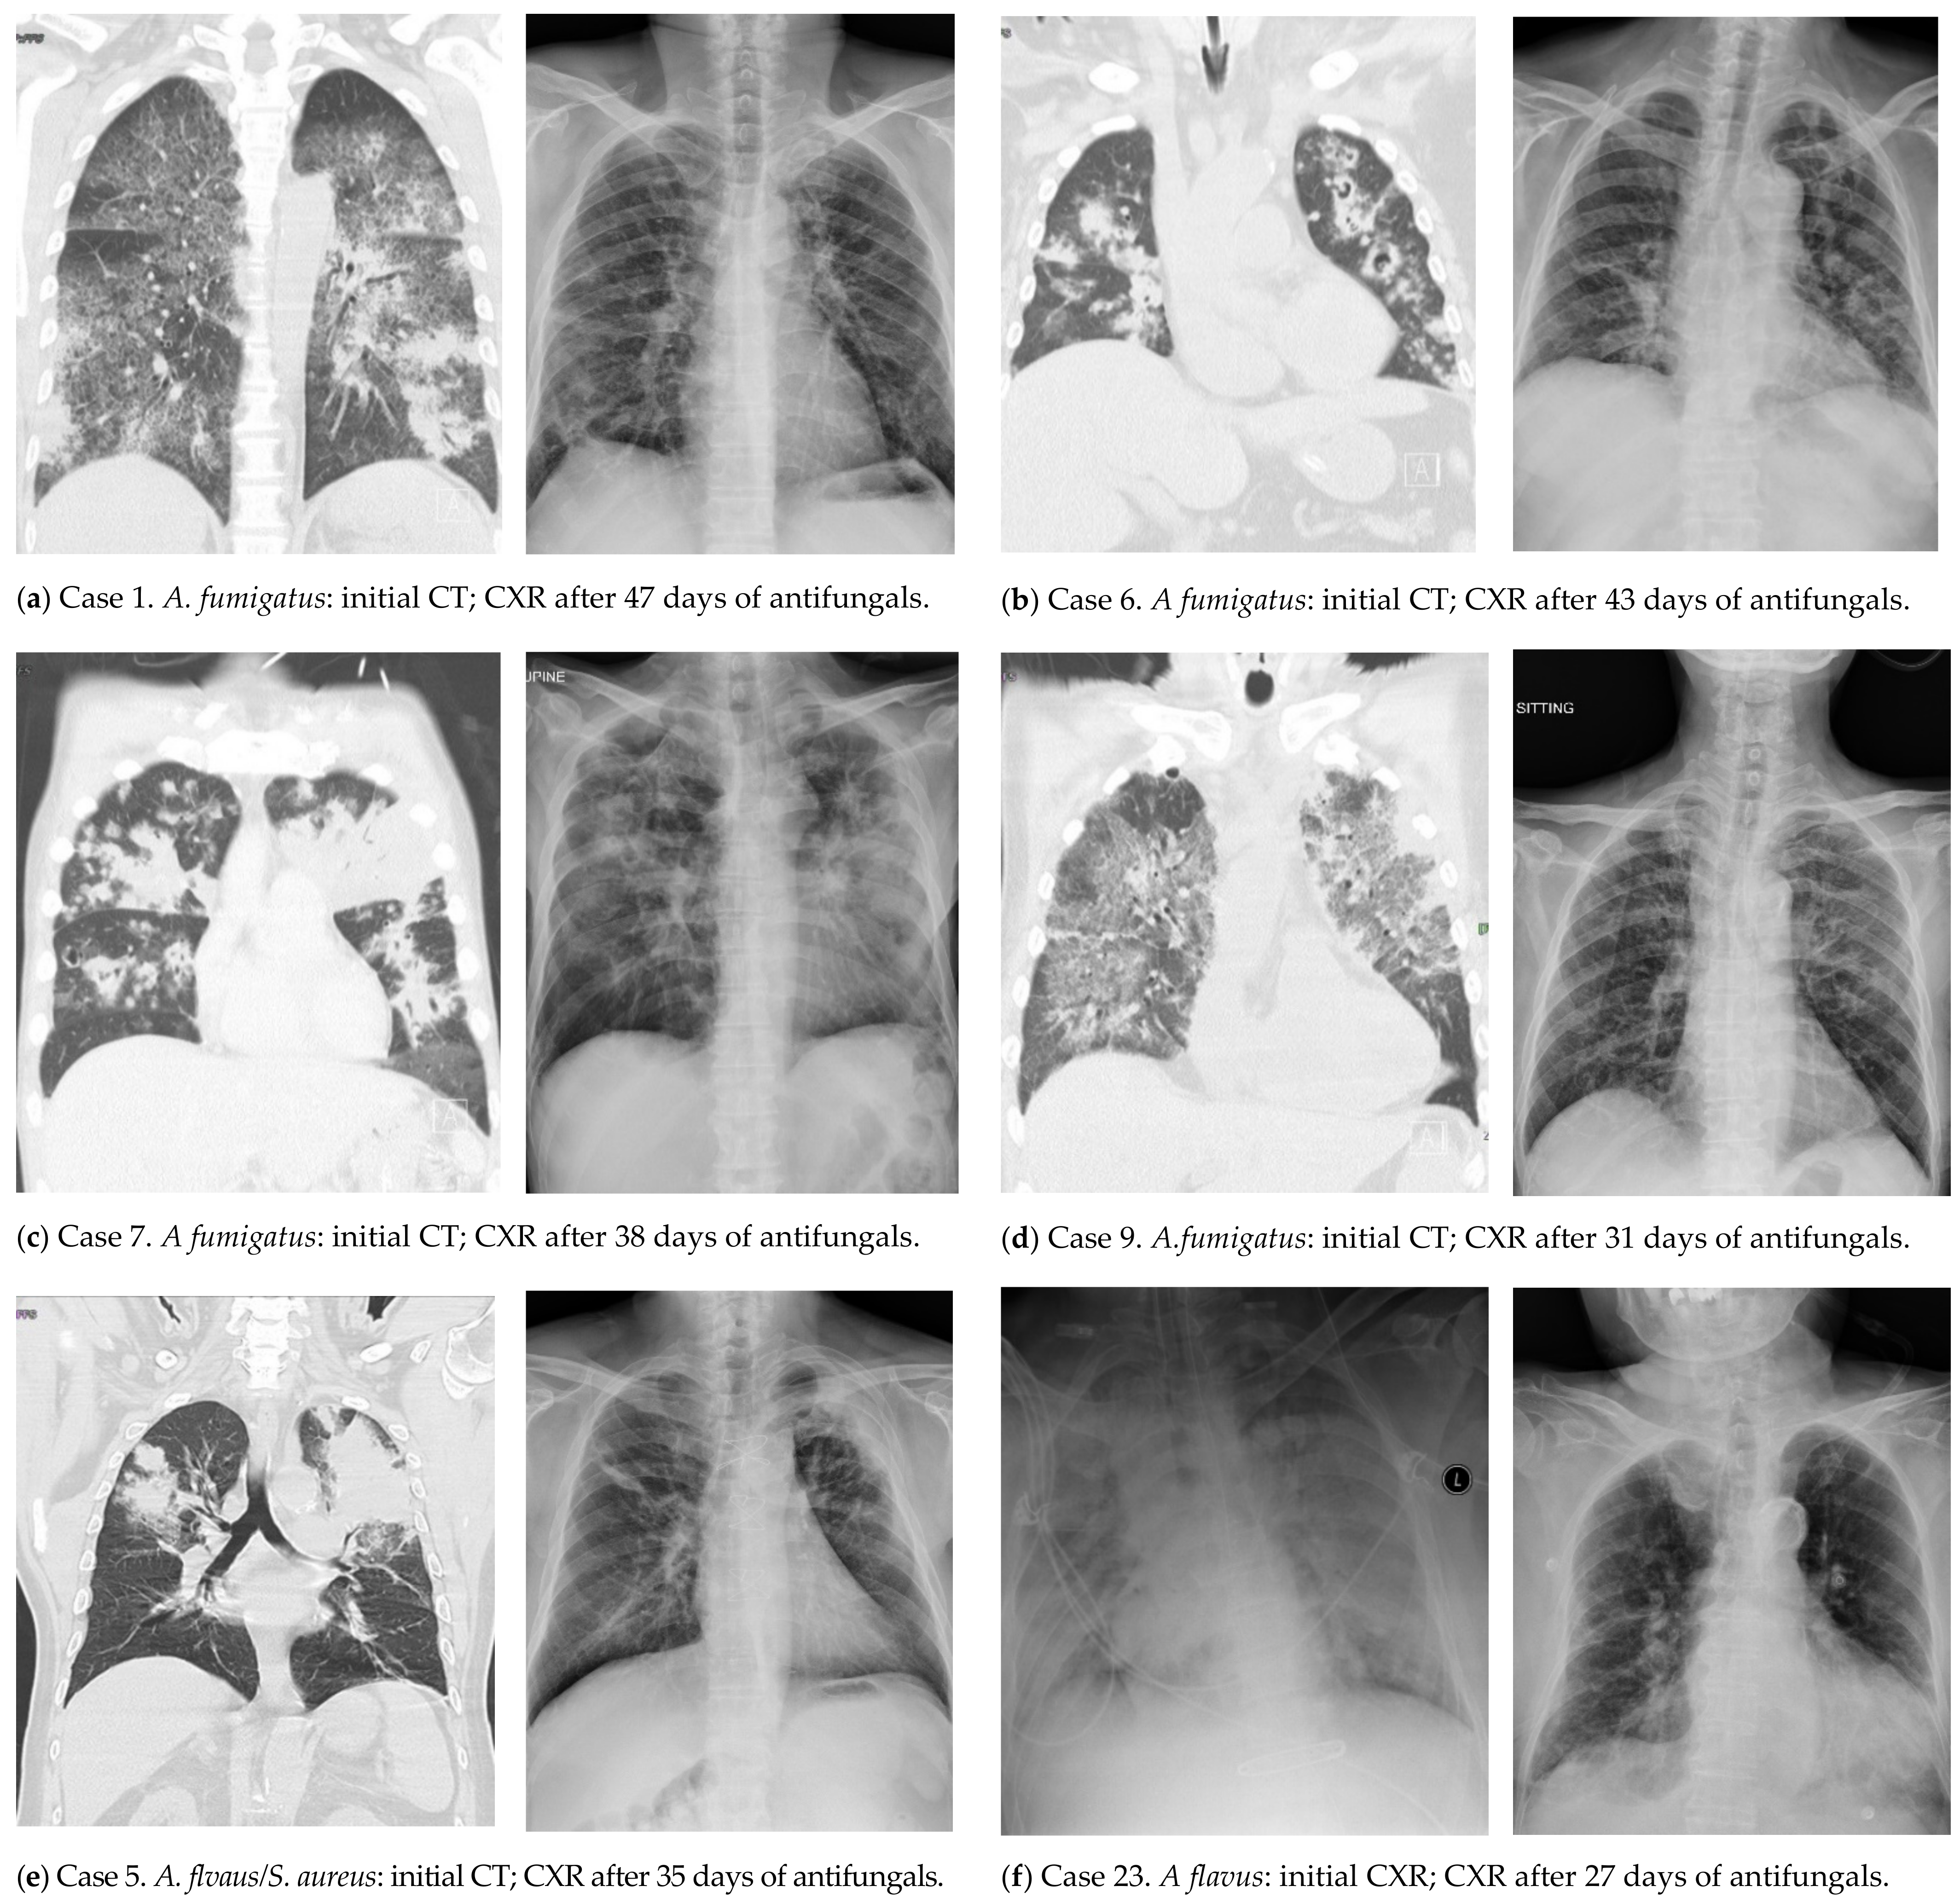

| 1 | 40+/M | CS, pancreatitis | B | 6 | 2.13 | nd | A. fumigatus | no | GGO, PBI, N, ws-C | VRC (5), CPF (5), VRC (36) | alive |

| 5 | 70+/M | CAD, CHF, DM | A (H1) | 0 | 0.36 | 3.16/n | A. flavus | SA | PBI, N, ws-C | VRC (51) | alive |

| 6 | 70+/M | CKD, COPD, MGUS | B | 4 | 4.26 | 5.07/n | A. fumigatus | no | PBI, N, cavities | VRC (51) | alive |

| 7 | 50+/M | DM | A (H3) | 6 | 0.71 | 5.25/n | A. fumigatus | no | GGO, PBI, N, cavities, ws-C | VRC (42) | alive |

| 9 | 70+/M | CHF, CS-E, HBV/LC, HCC, lymphoma | A (H3) | 1 | 0.09 | 2.44/n | A. fumigatus | no | GGO, PBI, N, ws-C | VRC (28) | alive |

| 23 | 80+/F | HTN | A (H1) | 4 | 0.35 | 6.65/y | A. flavus | no | (P, N, ws-C) | VRC (42) | alive |